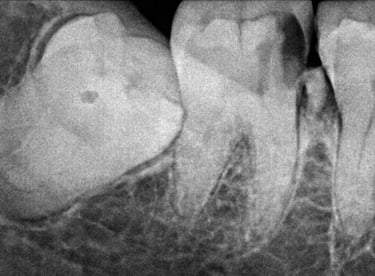

Q8. Do you use X-rays before tooth extraction?

Yes, dental X-rays are taken before extraction to assess the tooth position, root structure, and surrounding bone, ensuring safe and precise treatment.

All images shown here represent real clinical cases of teeth extractions done at our dental clinic with patient consent.

Illustrative images and similar real clinical cases requiring tooth extraction